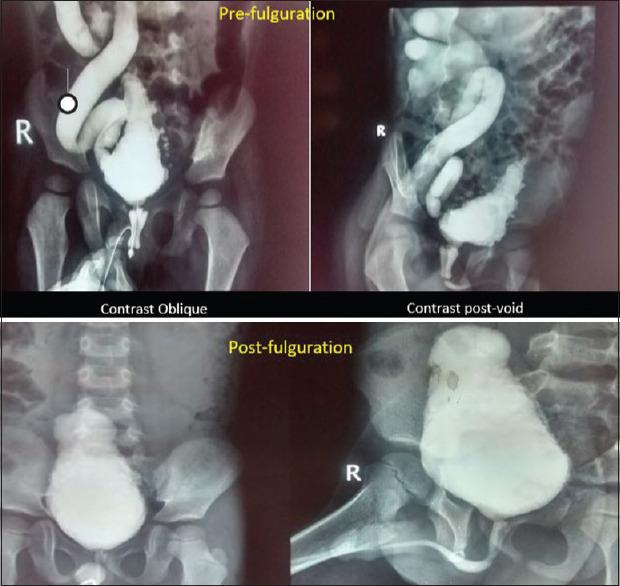

Posterior urethral valves (PUV) is the commonest obstructive uropathy with varied consequences. Though valve fulguration is the treatment of choice, appropriate bladder management modifies outcome and includes rational use of anticholinergics. Here, we aim to evaluate the effects of oxybutynin on the bladder and urinary tract morphology and function. Concurrently, we document adverse effects encountered, patient compliance, and medication adherence.

A retrospective study of children below 5 years of age (2012-2017) post fulguration and on oxybutynin for at least 6 months. Patient demographics, clinical features, renal ultrasound, micturating cystourethrogram, dimercaptosuccinic acid scan, adverse effects, and pill count for medication adherence were collated.

48 children below the age of 5 years were included, and 12 were excluded either due to the presence of concomitant problems or were not on oxybutynin. Of the 36, four were lost to follow-up and one had died due to an unrelated condition. Thus, a total of 31 children were analyzed. At follow-up, 28/31 patients were asymptomatic, two had daytime incontinence, and one had recurrent urinary tract infection. All patients except one have preserved renal function tests. On ultrasonography, hydroureteronephrosis worsened in only 1/25 children and two showed significant post void residues. The resolution of vesicoureteral reflux was noted in almost 50%. 4/31 renal units had progressive scars. Only two parents defaulted medication. Urodynamic study done in half of these children showed stable bladder pressures except in two.

Oxybutynin therapy following adequate valve fulguration aids upper tracts preservation by stabilizing deranged bladder dynamics. The medication is well tolerated with minimal or no side effects.

后尿道瓣膜(PUV)是最常见的梗阻性泌尿系统疾病,后果多样。尽管瓣膜电灼术是首选治疗方法,但适当的膀胱管理可改善预后,其中包括合理使用抗胆碱能药物。在此,我们旨在评估奥昔布宁对膀胱及尿路形态和功能的影响。同时,我们记录所遇到的不良反应、患者依从性和药物依从性。

对2012年至2017年接受电灼术且服用奥昔布宁至少6个月的5岁以下儿童进行回顾性研究。整理患者的人口统计学资料、临床特征、肾脏超声、排尿性膀胱尿道造影、二巯基丁二酸扫描、不良反应以及药物依从性的药丸计数。

纳入48名5岁以下儿童,12名因存在合并问题或未服用奥昔布宁而被排除。在这36名儿童中,4名失访,1名因无关疾病死亡。因此,共分析了31名儿童。随访时,31名患者中有28名无症状,2名有日间尿失禁,1名有复发性尿路感染。除1名患者外,所有患者的肾功能检查均正常。超声检查显示,仅1/25的儿童肾盂输尿管积水加重,2名儿童有明显的残余尿量。近50%的患者膀胱输尿管反流得到缓解。31个肾单位中有4个出现进行性瘢痕。只有2名家长未按时服药。对其中一半儿童进行的尿动力学研究显示,除2名儿童外,膀胱压力稳定。

在充分的瓣膜电灼术后,奥昔布宁治疗有助于通过稳定紊乱的膀胱动力学来保护上尿路。该药物耐受性良好,副作用极小或无副作用。